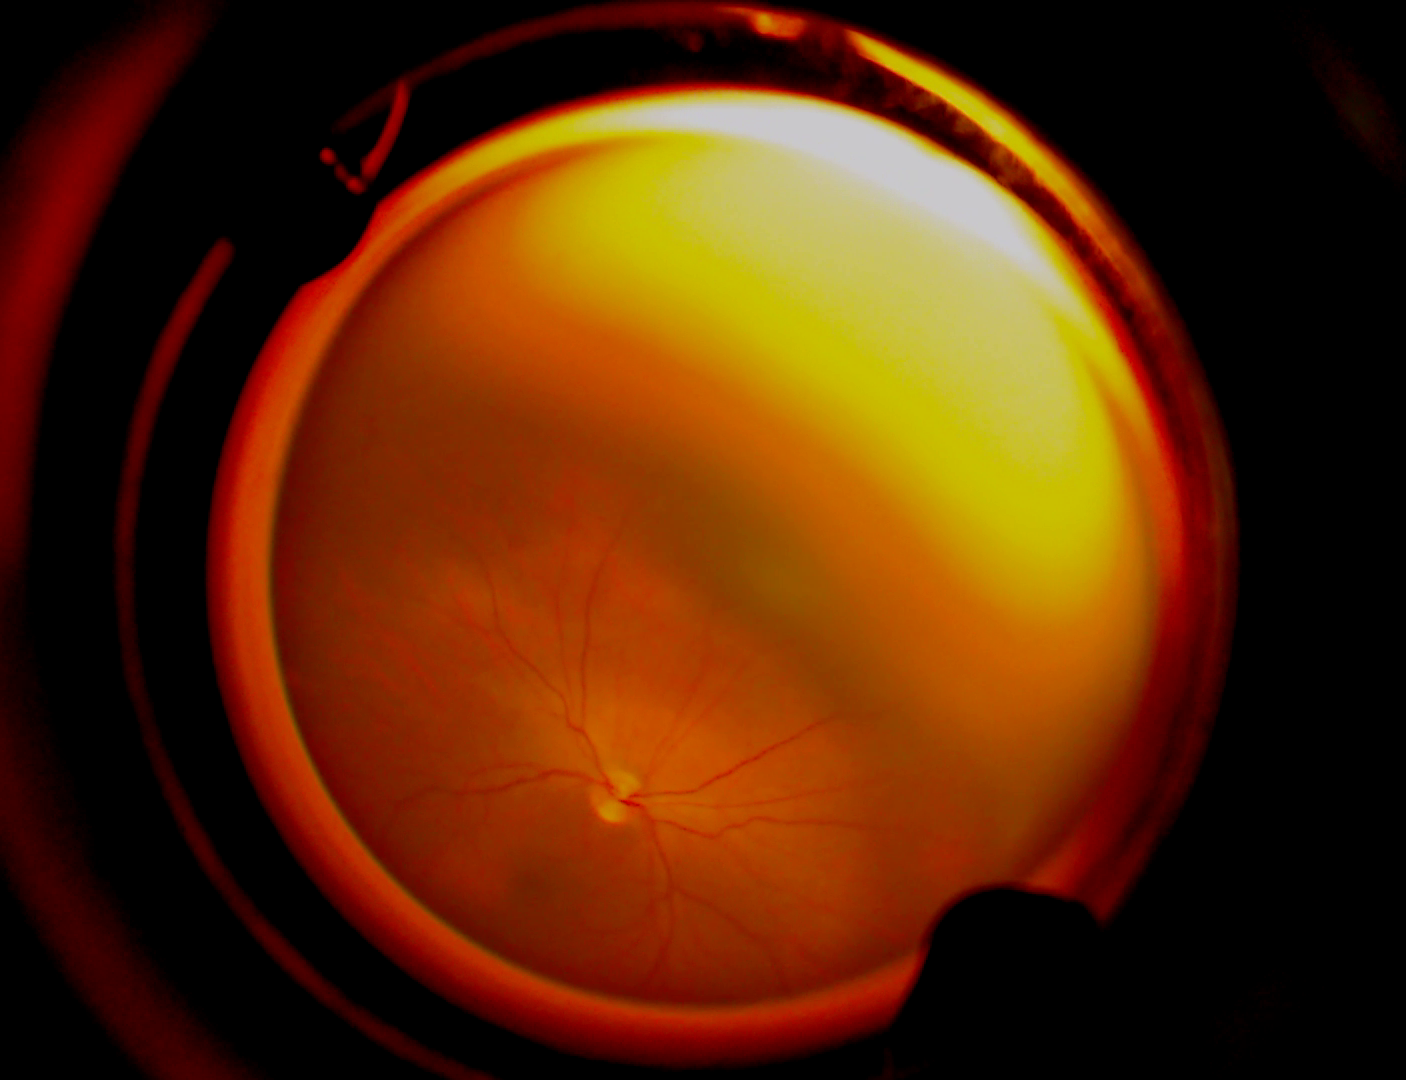

VART, un avanzado dispositivo de telemedicina con inteligencia artificial, se erige como una herramienta vital en la identificación de anomalías y enfermedades oculares en bebés prematuros. Este sistema pionero permite la observación detallada del fondo del ojo en neonatos, brindando un campo visual de 160° y recopilando imágenes de la retina para el diagnóstico preciso de retinopatía en esta vulnerable población.